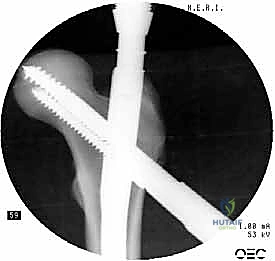

1. المسمار النخاعي الرئيسي (Intramedullary Nail): مسمار طويل يمتد داخل القناة النخاعية لعظمة الفخذ.

2. المسمار الرأسي/العنقي (Cephalic/Lag Screw): مسمار سميك وقوي يمر من خلال الجزء العلوي للمسمار النخاعي، ويدخل في عنق ورأس عظمة الفخذ لتثبيت الكسر الرئيسي.

3. مسامير الغلق السفلية (Distal Locking Screws): مسامير صغيرة تُثبت أسفل المسمار النخاعي لمنعه من الدوران أو الانزلاق داخل العظم.

هذا التصميم العبقري يجعله أقوى نظام تثبيت متوفر حالياً، حيث يمر محور تحمل الوزن عبر المسمار الموجود داخل العظم، مما يجعله مقاوماً للكسر والانحناء، ويسمح للمريض بالاعتماد على ساقه في وقت قياسي.

2. الرد المغلق (Closed Reduction)

باستخدام جهاز الأشعة السينية المرئية المستمرة (C-Arm Fluoroscopy) داخل غرفة العمليات، يقوم الدكتور هطيف بإعادة العظام المكسورة إلى محاذاتها التشريحية الصحيحة عن طريق الشد والتدوير الخارجي للساق، وكل ذلك يتم مراقبته على الشاشة بدقة متناهية.

5. تثبيت عنق ورأس الفخذ (المسمار الرأسي)

من خلال ذراع توجيه متصلة بالمسمار الرئيسي، يتم إحداث ثقب في عنق ورأس عظمة الفخذ. يتم إدخال المسمار الرأسي (Cephalic Screw) السميك ليمسك برأس الفخذ بقوة ويسحبه نحو المسمار الرئيسي، مما يضغط الكسر (Compression) ويحفز التئام العظام بسرعة.

6. التثبيت السفلي (Distal Locking)

لضمان عدم دوران العظمة حول المسمار، يتم إدخال مسمار أو مسمارين صغيرين في الجزء السفلي من المسمار النخاعي عبر شقوق جلدية دقيقة جداً (لا تتجاوز 1 سم).